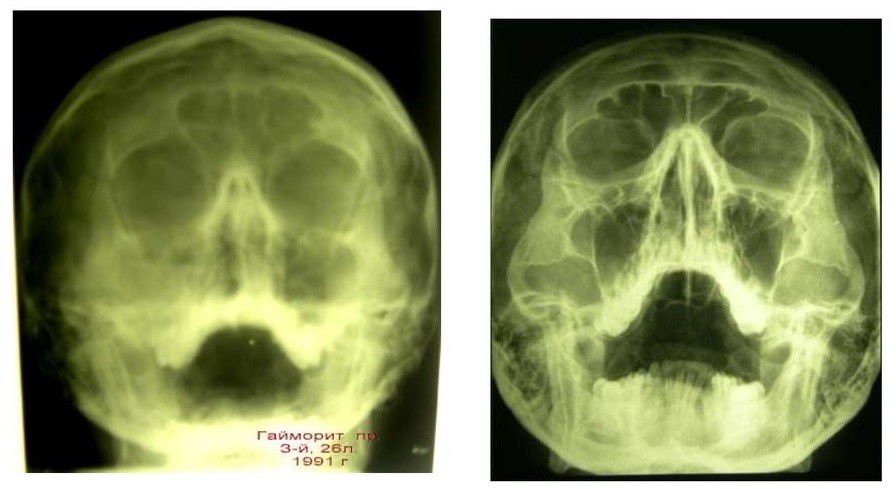

Обычно рентгенографию позвоночника проводят в двух взаимно перпендикулярных плоскостях: прямой (с переднезадней проекцией) и боковой. Однако анатомические особенности различных отделов позвоночника требуют применения косых и дополнительных проекций.

На рентгеновском снимке плотная костная ткань отображается белым цветом, в то время как мягкотканевые структуры, такие как мышцы и подкожно-жировая клетчатка, представлены различными оттенками серого.

При изучении рентгенограмм позвоночника врач-рентгенолог обращает внимание на следующие аспекты:

- Изгибы позвоночного столба. Физиологическими изгибами считаются шейный и поясничный лордозы (изгибы, направленные вперед), а также грудной и крестцовый кифозы (изгибы, направленные назад). Увеличение этих изгибов может указывать на патологию. Отклонение позвонков влево или вправо называется сколиозом;

- Структура и форма позвонков. В норме они выглядят как участки светлого цвета с четким контуром. Тело позвонка на рентгене напоминает прямоугольник с закругленными краями, на которых не должно быть костных разрастаний (остеофитов). В прямой проекции можно увидеть поперечные отростки, которые направлены в стороны от дуги позвонка, а также остистый отросток, расположенный посередине дуги. Остистые отростки в боковых проекциях образуют непрерывную линию;

- Расстояние между позвонками. В норме эти промежутки должны иметь примерно одинаковую высоту, увеличиваясь к поясничному отделу;